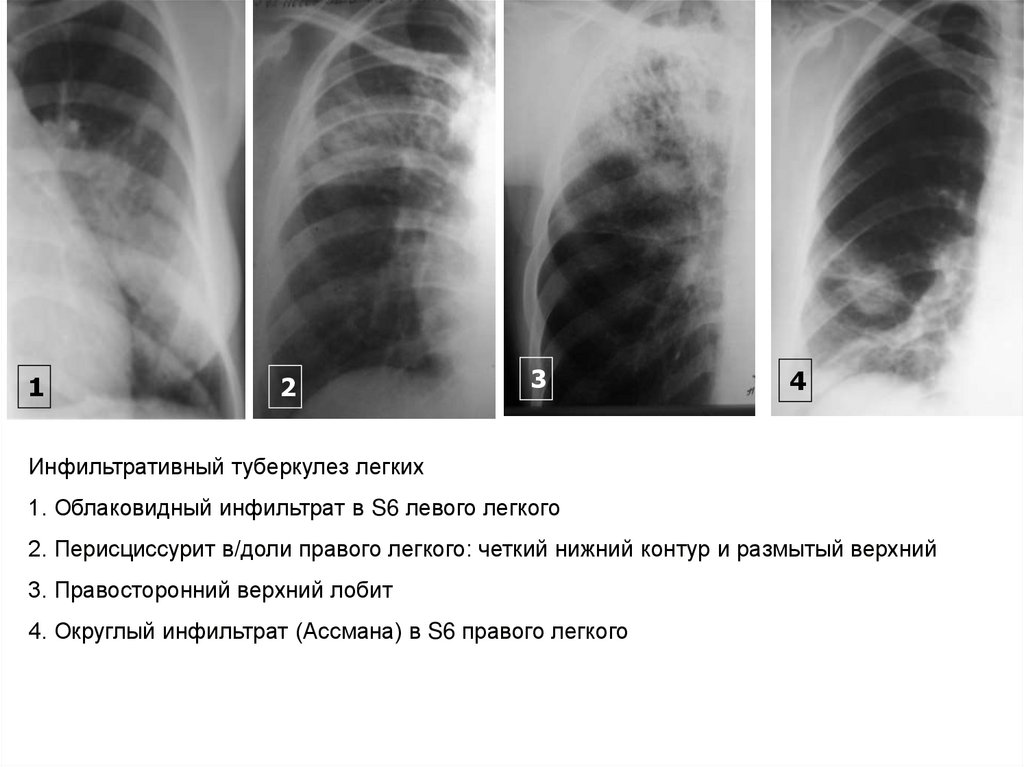

Симптомы и лечение инфильтративного туберкулеза легких

Раздел: Снимки-откровения